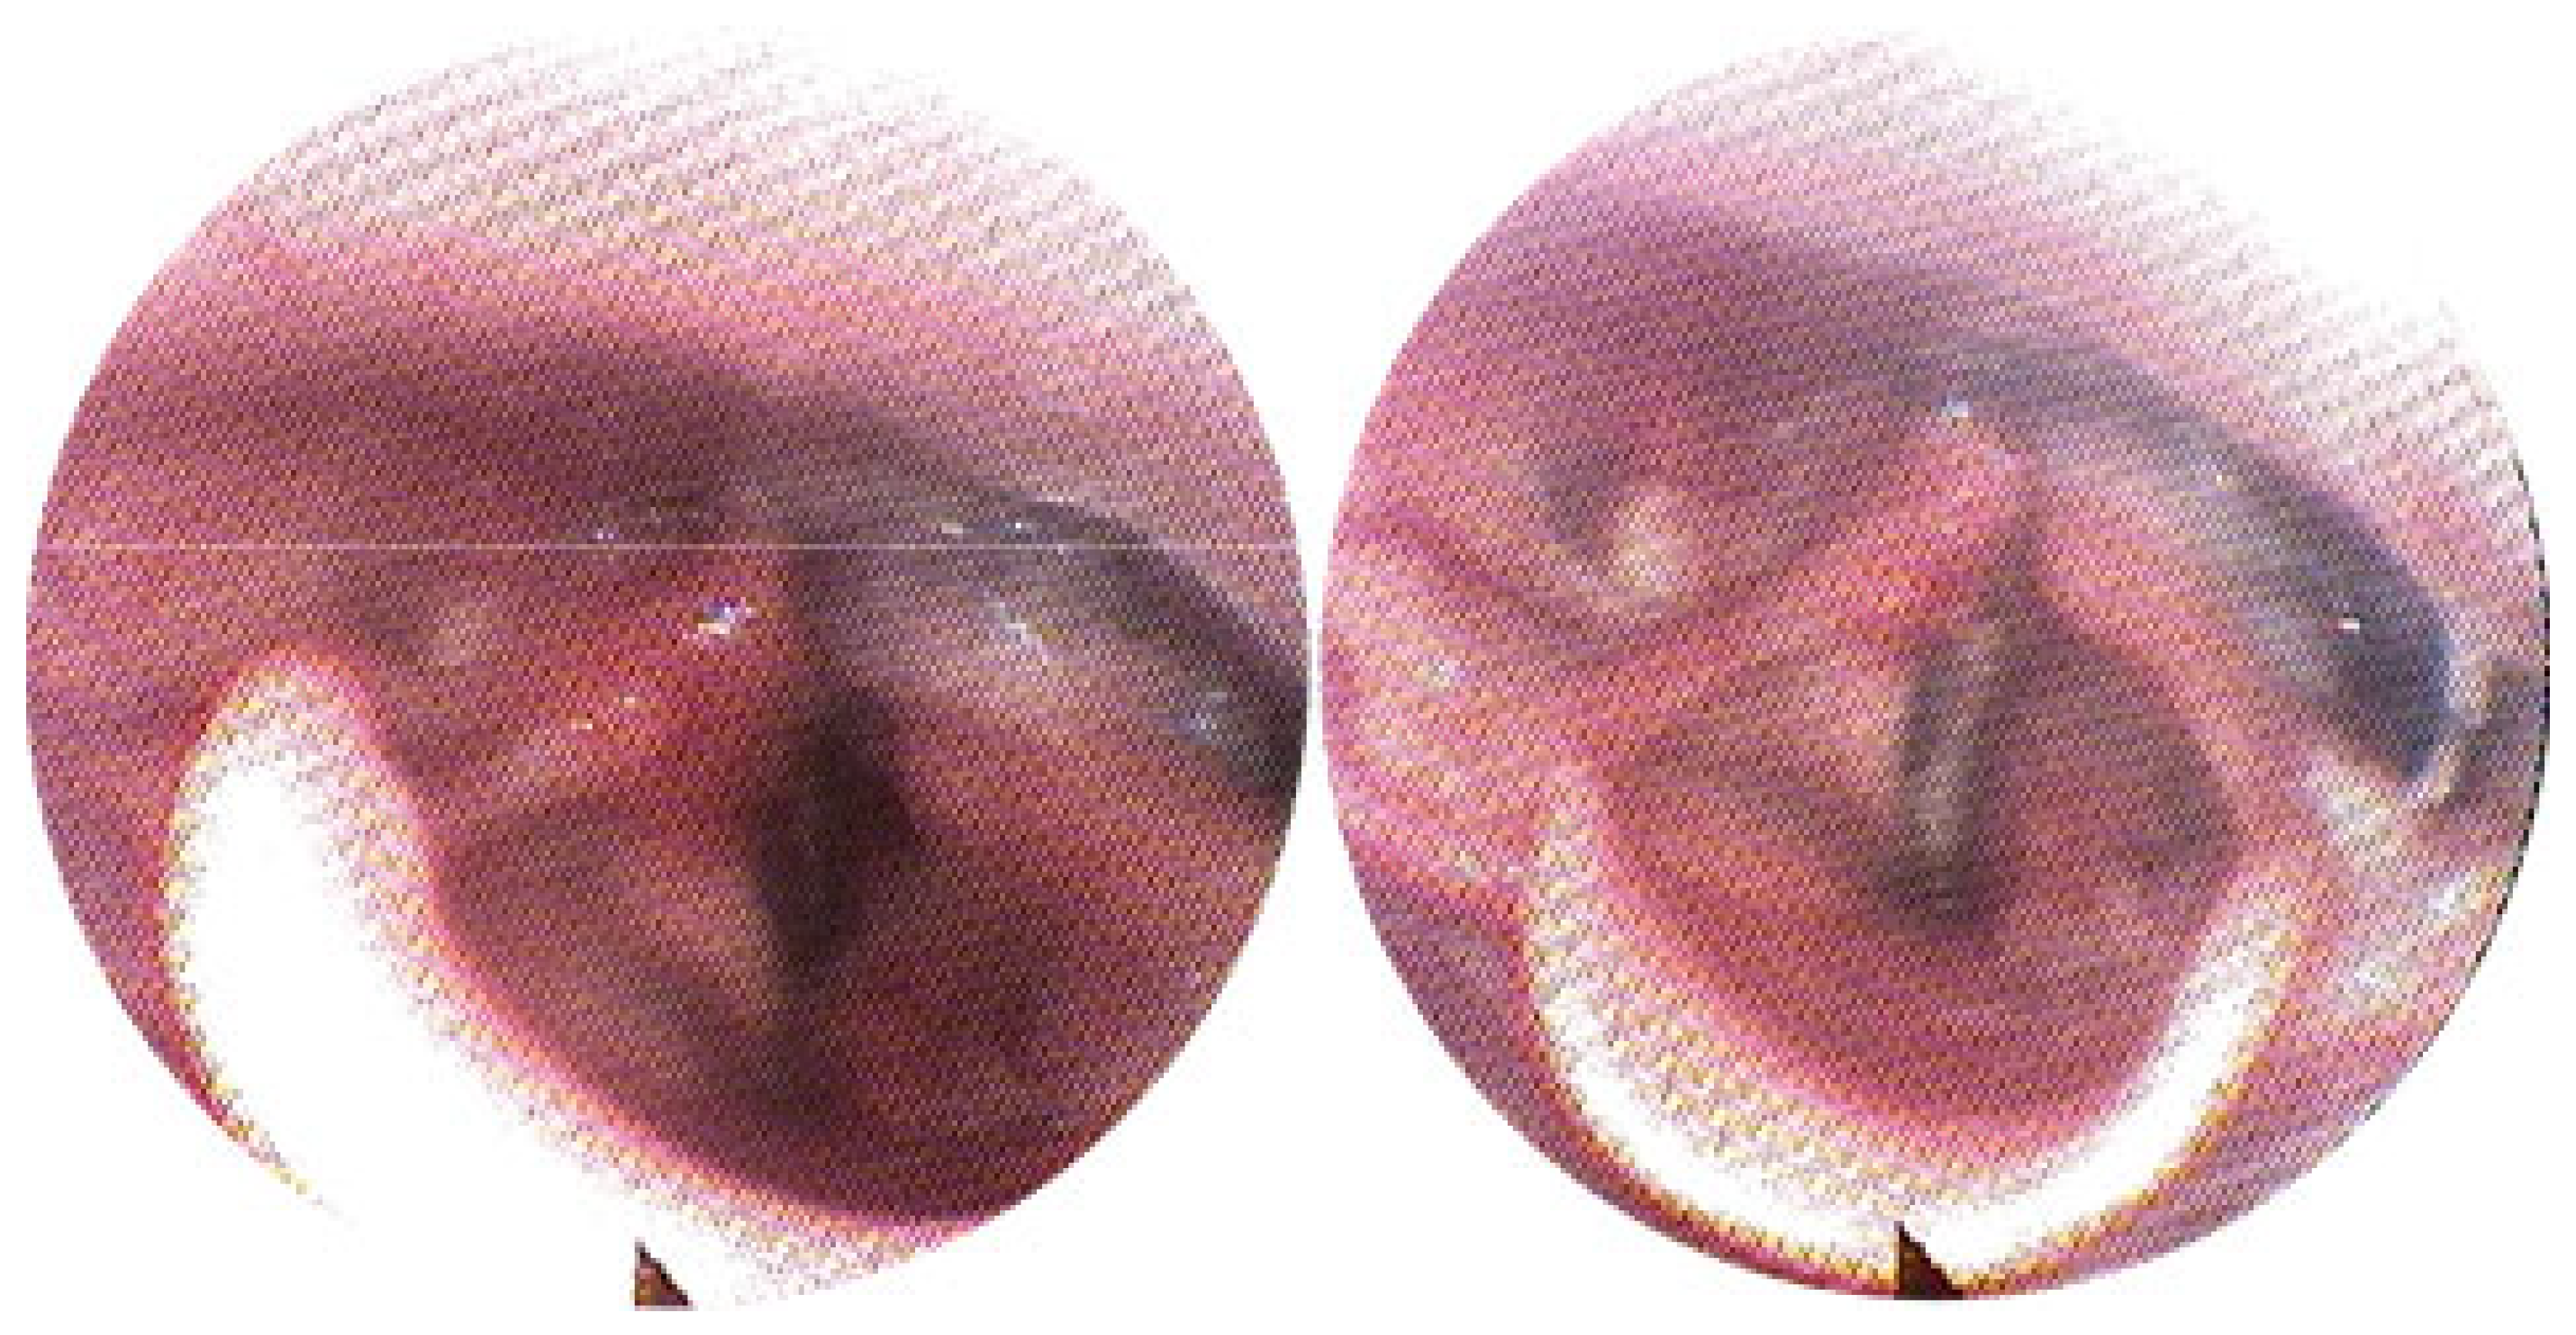

3.1. Magnetic Resonance Imaging (MRI) Findings

3.2. Clinical Outcomes